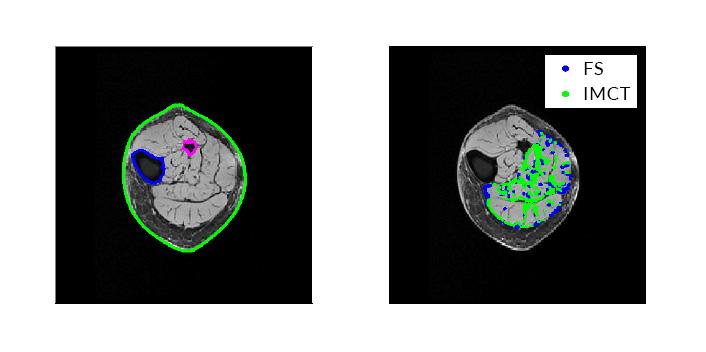

From left: Outer contours and bone contours obtained from segmentation of MRI; and points showing intramuscular connective tissue and intra-muscular fat saturation.